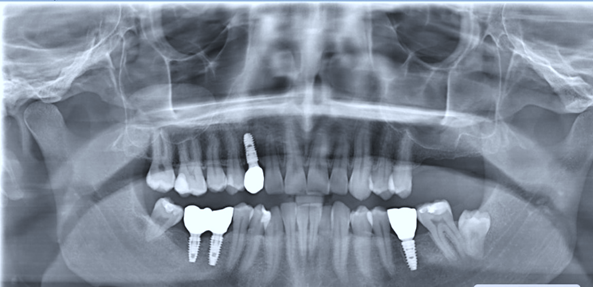

Tooth 4.8 is planned for extraction. Which radiographic findings suggest an increase in the degree of difficulty of the extraction?

13. (Select ONE OR MORE correct answers.)

Tooth 1.8 is planned for surgical extraction. Which radiographic findings suggest an increase in the degree of difficulty of the extraction?

Tooth 2.8 is planned for surgical extraction. Which radiographic findings suggest an increase in the degree of difficulty of the extraction?